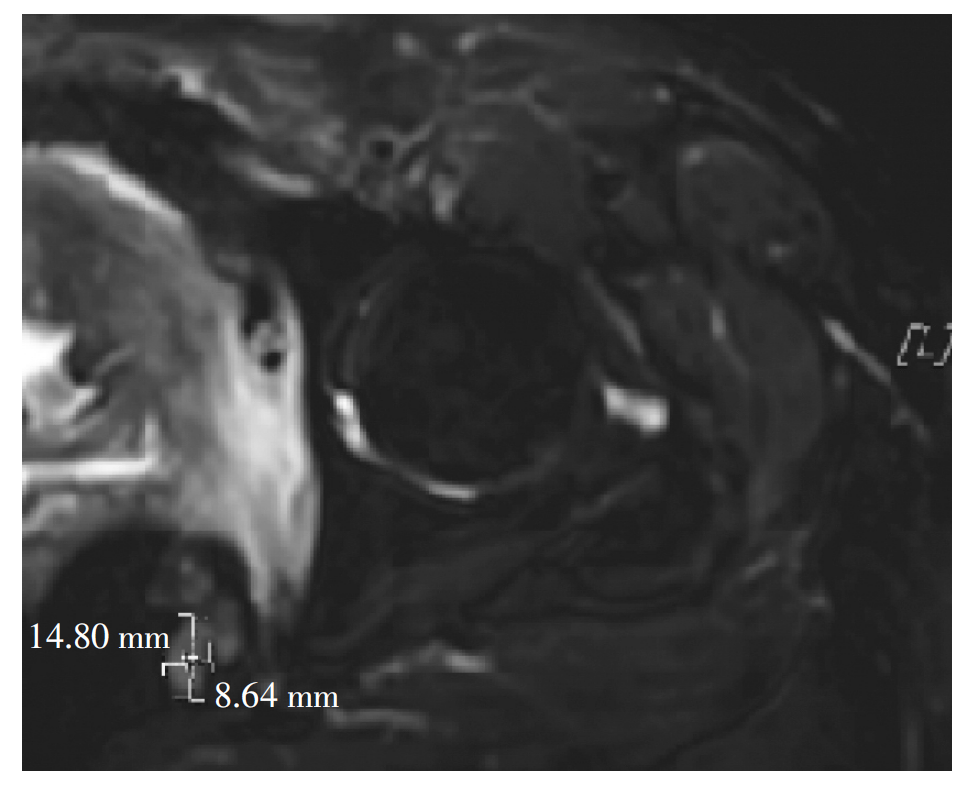

宫颈癌的发病率高居妇科恶性肿瘤之首,目前手术仍然是早期宫颈癌有效的治疗方法。但宫颈癌具有较高的复发率和远处转移能力,晚期预后差,治疗选择有限。报告1例宫颈癌根治术和放化疗联合治疗后仍复发,出现膀胱阴道瘘和直肠阴道瘘并发严重感染的患者,经卡度尼利单抗单药及联合化疗治疗取得了生存获益,旨在为复发性宫颈癌的治疗提供新思路。

The incidence rate of cervical cancer is the highest among gynecological malignancies. At present, surgery is still an effective treatment for early-stage cervical cancer, but cervical cancer has a high recurrence rate and distant metastasis, poor prognosis in advanced stages, and limited treatment options. This article focuses on a case with recurrence of cervical cancer despite radical hysterectomy and combined chemotherapy and radiotherapy, who developed vesicovaginal fistula and rectovaginal fistula with severe infection, and achieved a survival benefit by treatment with cadonilimab monotherapy and combination chemotherapy. It aims to provide new ideas for the treatment of recurrent cervical cancer.